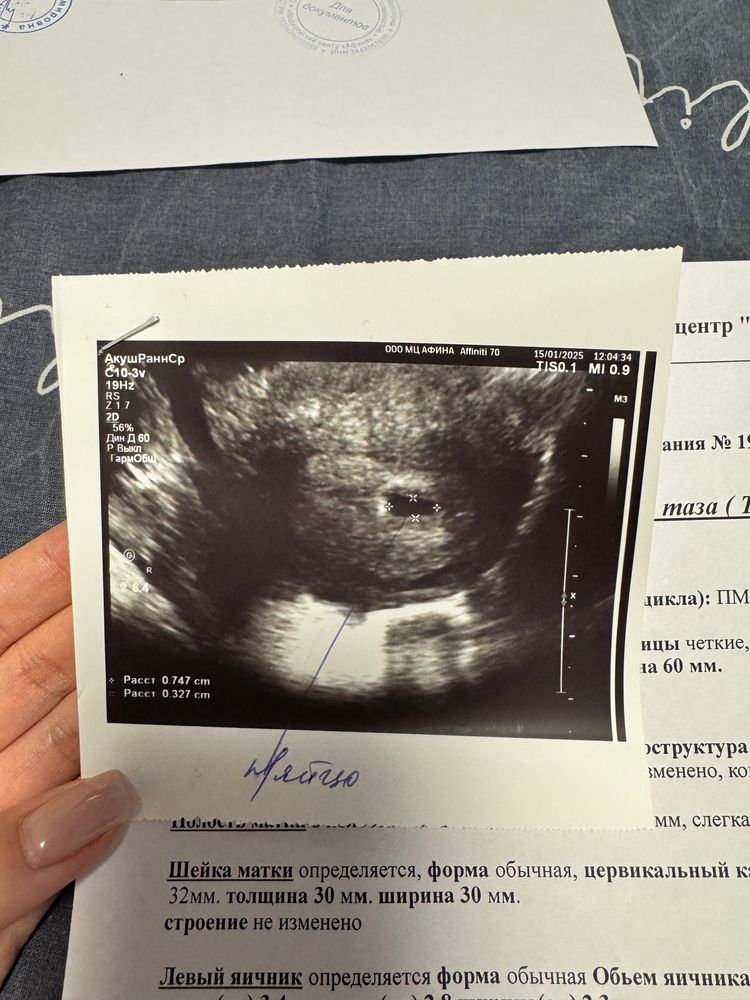

Анни, Пя 14 мм, жм 0.37. Ктр 0.5.

Анни, тонус конечно влияет, стенка Пя из-за этого напряжения немного изогнута. Но это не страшно, выправится потом. Я читала, что у многих до 2 см Пя ещё кажется пустым. Всё у вас появится, не переживайте 😉🤗